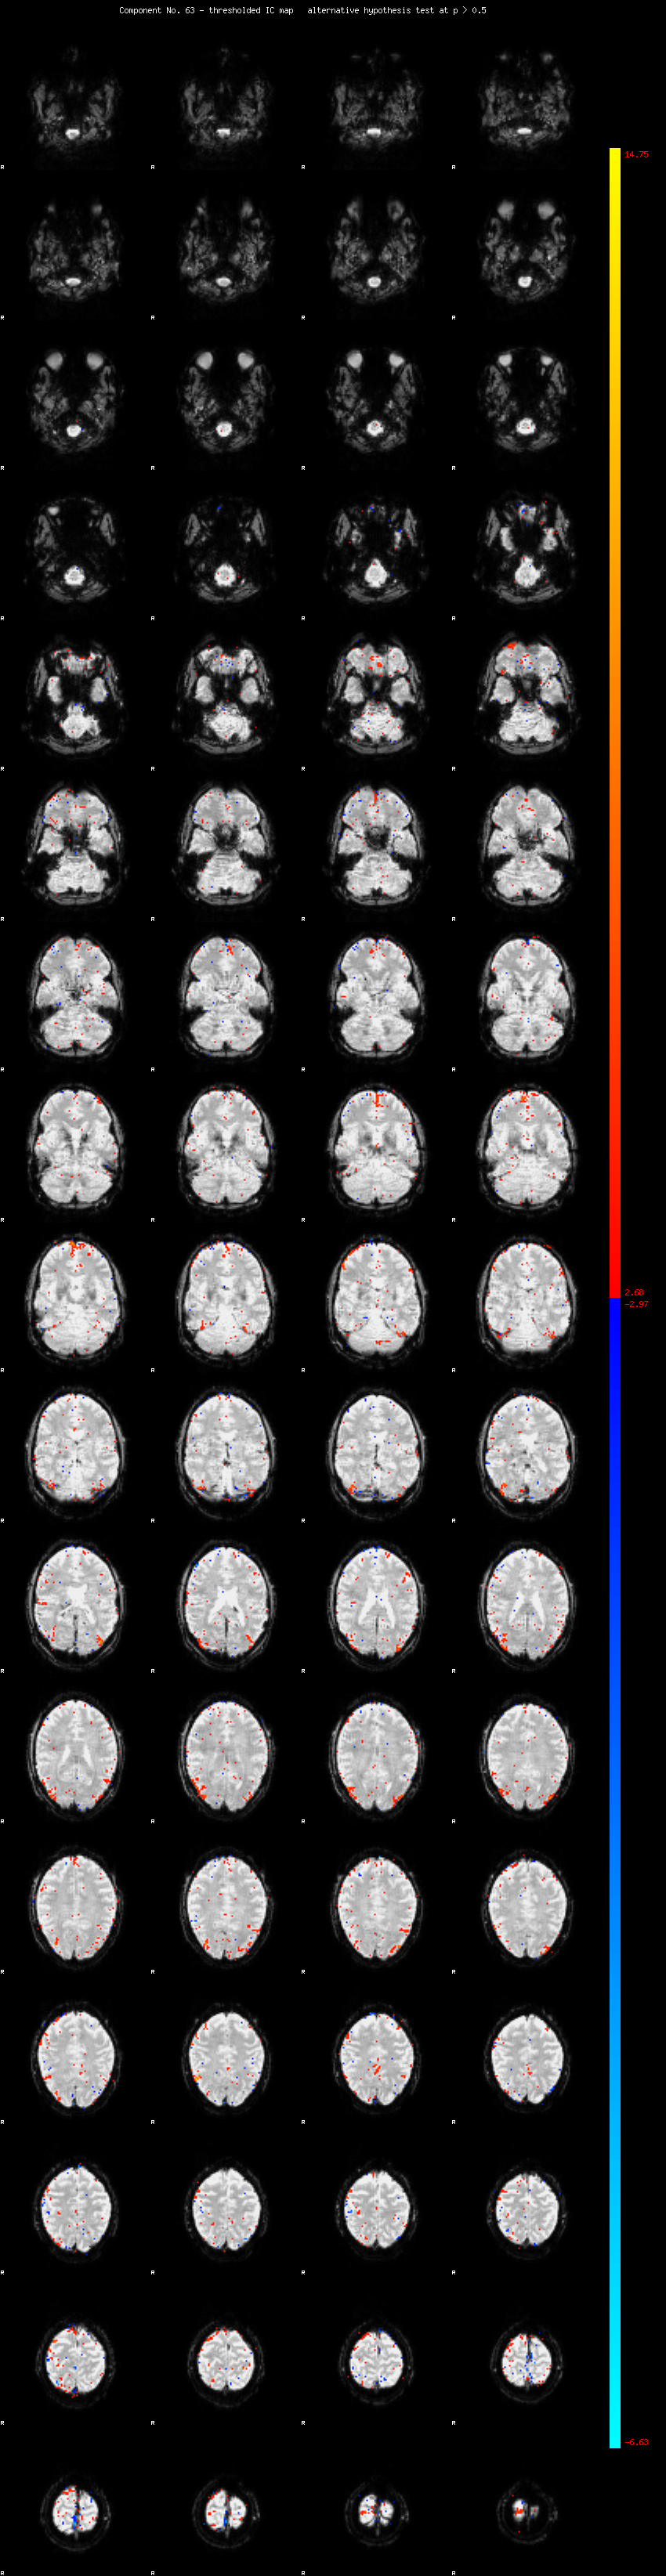

MELODIC Component 63

0.85 % of explained variance;     0.56 % of total variance